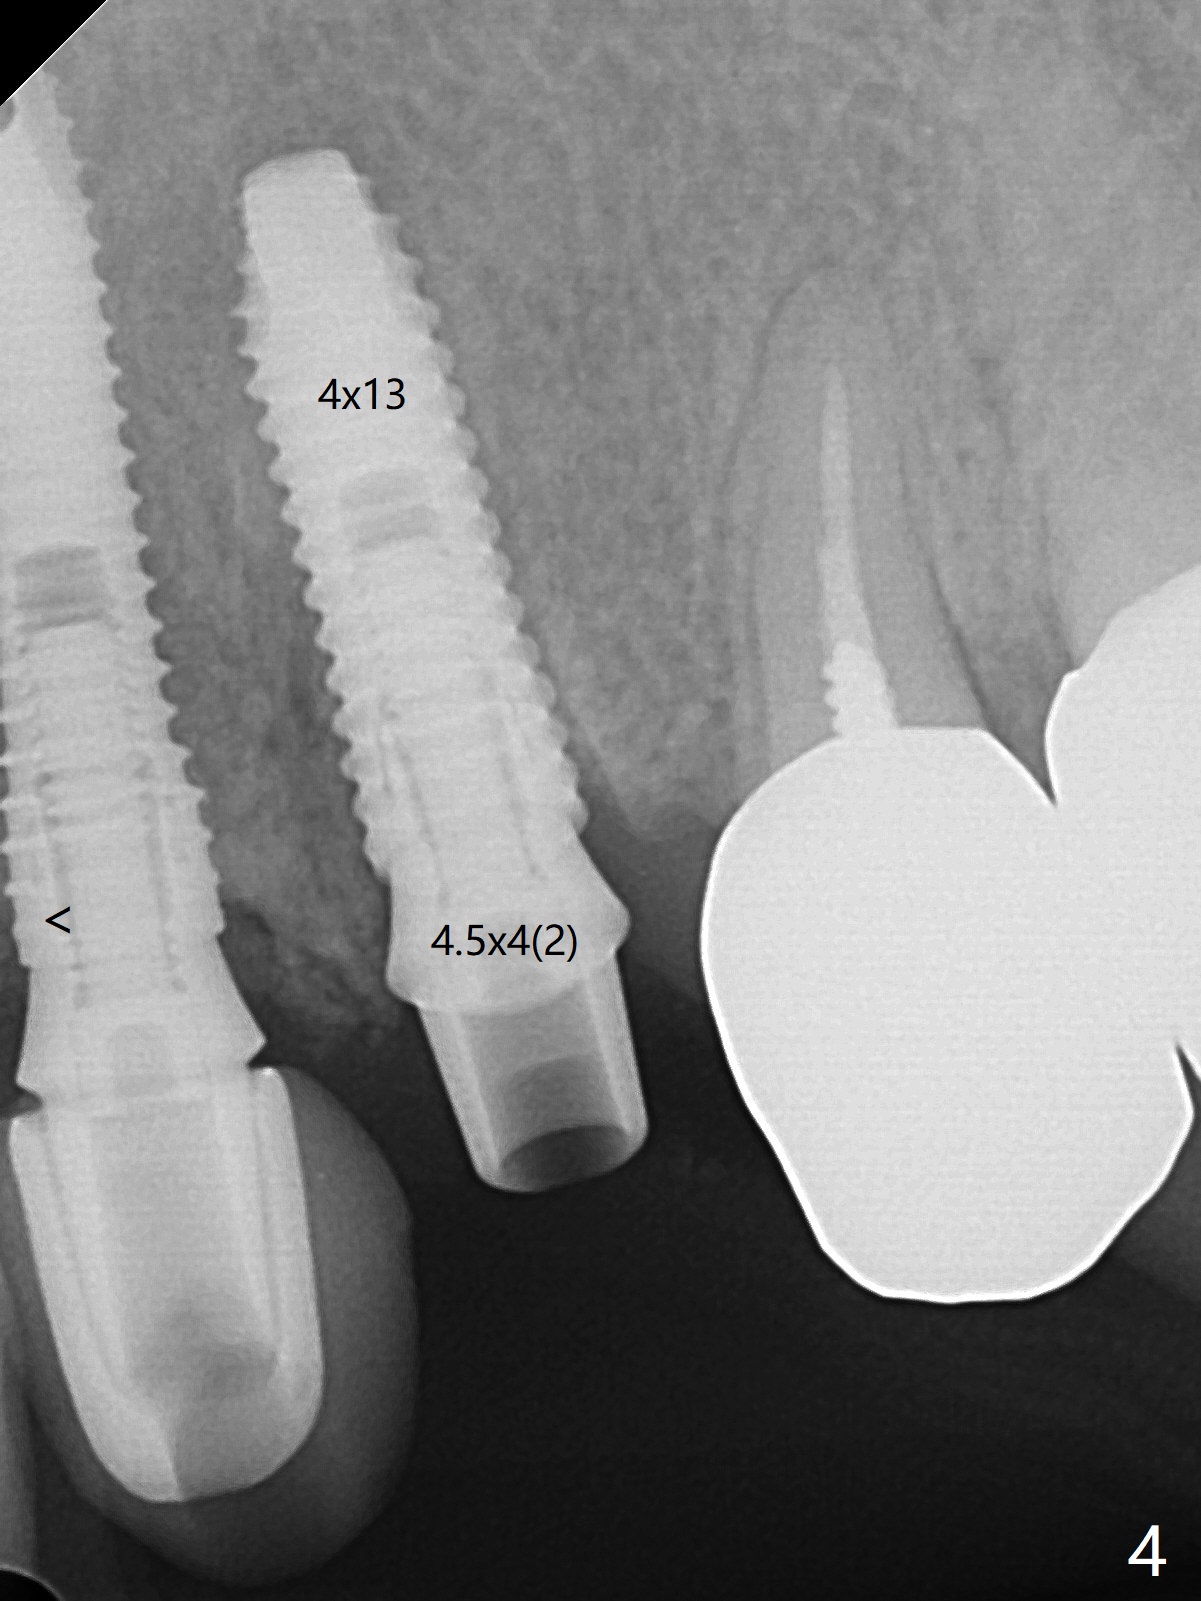

52岁女左上4颊侧牙龈显著肿胀(图一:*(颊侧骨板缺失))伴有瘘道(<),拔除前,在3植牙牙冠切缘舌侧形成开口(图二:*,准备纠正基台不全就位(<);4初步钻洞不正。改变钻头方向后(图三),完成植体放置(图四),并且安置修复基台(4.5x4(2))。磨去3牙冠近中面(图六:*),牙冠和基台反时针旋转(图六:弯箭头),基台完全就位(图四:箭头),调𬌗后,制作4临时牙冠(图六),放置后者前,覆盖半张PRF膜(促进下面粘性骨粉愈合)。图五,六颊侧隆起是因为下面放置许多粘性骨粉。图七是术前CT3D图像(冠状切面),显示颊侧(B),腭侧(P)牙根。拔牙后显示中隔(图八:S),植体植入腭侧窝(图九:绿色),四面骨质包绕,包括中隔;为了修复颊侧骨板,首先放置半张PRF膜(红色)紧贴颊侧骨板腭侧/牙龈,防止骨粉从瘘道流失,然后放置粘性骨粉(图十:粉红色)。术后2.5月3颊侧牙龈仍然红肿(图十一,十二:*),可能与基台袖太短有关(2毫米,图二至四),所以更换袖3毫米的基台(图十三)。术后四个月(牙冠粘固)3颊侧牙龈炎症明显减退(资料没有显示)。术后2.5月4颊侧骨板没有塌陷(图十二,与术后即刻对比(图六))。3基台放置太颊侧,所以在牙冠腭侧制作小的开口(图十四:>),让多余粘固剂流出。取模前3螺丝就拧紧(35Ncm),而4由于有大的开口,粘固后才拧紧(30Ncm)。两个邻牙其中一个可以取出,容易去除另外一个牙冠残余粘固剂。